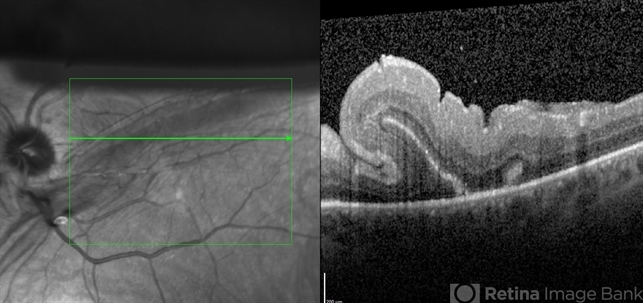

- Condition/keywords

- optical coherence tomography (OCT), retinal fold

- Matt Poe, COA. Northwest Arkansas Retina Associates, Springdale, AR.

- Optical coherence tomography system

- This patient developed a retinal fold following a retinal detachment repair. The patient underwent another retinal detachment surgery to fix the retinal fold. The patient's retina was fixed and did well post-operative.